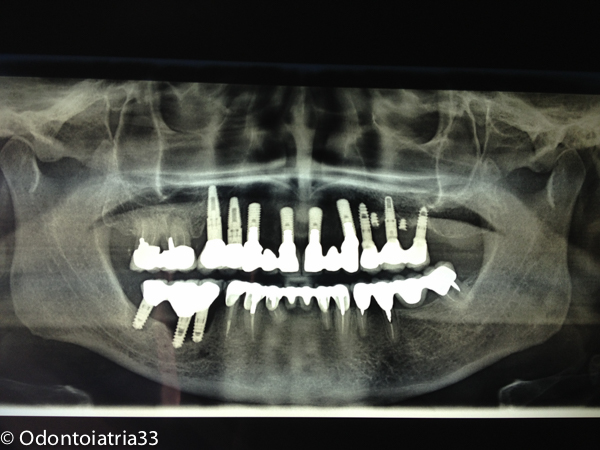

Valutato il quadro clinico e radiografico abbiamo ritenuto il caso di trattare la paziente (che non voleva rimettere mano alle riabilitazioni posteriori e inferiori eseguite presso un altro studio poco addietro), con una chirurgia preprotesica di rimodellamento osseo,contestualmente all'inserimento degli impianti, mediante frese carotatrici, che ci consentissero di prelevare osso prezioso da posizionare eventualmente nelle aree deficitarie, e frese rotanti a rosetta in tungsteno per rifinire i bordi; il tutto sotto abbondante irrigazione di fisiologica sterile al fine di scongiurare un surriscaldamento eccessivo della struttura ossea e quindi un suo critico e non prevedibile riassorbimento. Sono stati fatti scarichi di rilascio laterali molto corti, l'incisione è stata di tipo crestale lievemente palatale al fine di mantenere il massimo della vascolarizzazione e struttura gengivale aderente. La paziente viene trattata nel post-operatorio con terapia antibiotica iniziata dalla sera prima dell'intervento ( 1gr di amoxicillina e acido clavulanico ogni 12 ore per 6 giorni) con sciacqui con chlorexidina digluconato 0,12% 3 volte al dì per 10 giorni, Arnica Montana in compresse sublinguali 5cps 3 volte al dì da tre giorni prima a tre giorni dopo l'intervento.

Trattandosi di guidare al contrario la morfologia ossea tramite rimodellamento abbiamo cercato di trovare un equilibrio fra necessaria riduzione ossea in senso volumetrico antero-posteriore /cranio-caudale e perdita di supporto sul labbro superiore con appiattimento del profilo, posizionando gli impianti un po' più vestibolarizzati e profondi,nonchè lavorando sui profili gengivali mediante provvisori a condizionamento tissutale.

I primi provvisori avvitati sono stati posizionati dopo 6 settimane dall'intervento chirurgico di inserimento implantare e rimodellamento. I provvisori avevano ancora per ragioni tecniche un rapporto di overjet da correggere poi con i definitivi.

Dopo 5 mesi di provvisori avvitati man a mano modificati la paziente è stata protesizzata con definitivi in zirconio e ceramica stratificata.